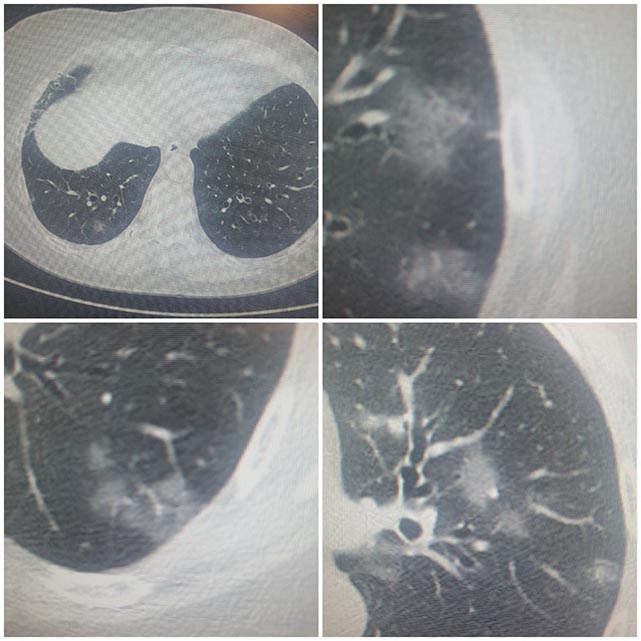

Samsun’da Covid-19 alarmı! Prof. Dr. Şevket Özkaya, “Son birkaç gündür uzun zamandır ilk kez bu hafta Covid-19'a bağlı akciğer tutulumları nedeniyle hastaneye yatışların da arttığını gördük" dedi.

Altınbaş Üniversitesi Göğüs Hastalıkları Anabilim Dalı Başkanı ve Gazete Gerçek yazarı Prof. Dr. Şevket Özkaya, “Covid-19'un 'flirt (flört)' varyantı olarak kayıtlara geçen bu yeni varyantın son günlerde özellikle Amerika’dan bildirilen Covid-19'un yeni varyantının Avrupa’ya doğru yayıldığını söylemiştik.

İlginç olarak Amerika'da atık sularda tespit edilen korona virüs miktarının arttığı bildirilmiş. Bizde de acil servislerde, polikliniklerde Covid-19 vakalarının bu ay başlarında artmaya başladığını görüyoruz.

Son birkaç gündür uzun zamandır ilk kez bu hafta Covid-19'a bağlı akciğer tutulumları nedeniyle hastaneye yatışların da arttığını gördük" dedi.